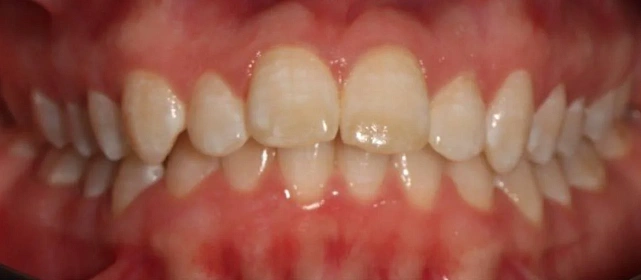

Прозрачные элайнеры 3D Smile на обе челюсти. Выровнять зубы и нормализовать смыкание. Основной набор — 34 капы. Срок — около 2 лет.

Лечение заняло 32 месяца (февраль 2023 — октябрь 2025). Понадобился один дополнительный набор из 28 кап — итого 62 капы. Параллельно проводилась профессиональная гигиена.

Решение: Поставили прозрачные элайнеры 3D Smile на обе челюсти. Начали с набора из 34 кап, но в процессе стало понятно, что для полной коррекции нужна доработка — заказали дополнительный набор из 28 кап. Это нормальная ситуация: организм реагирует на перемещение зубов индивидуально, и заранее предсказать точное количество кап до последней штуки невозможно. В итоге 62 капы за 32 месяца — зубы встали на место, смыкание пришло в норму. Параллельно следили за гигиеной, чтобы дёсны оставались здоровыми на протяжении всего лечения.